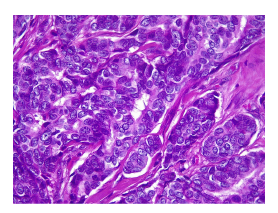

Con estos estudios fue remitida al Servicio de Oncología Clínica donde en el examen físico se documentó cicatriz en la región cervico-occipital lateral izquierda, con leve fibrosis, sin lesiones tumorales palpables o visibles en piel, tejidos blandos, cavidad oral, cervical, axilar o mamario. Se solicitó una revisión de la histopatología, y se hizo un nuevo panel de inmunohistoquímica con reporte positivo para sinaptofisina, cromogranina, BER-EP4, GATA3 y andrógenos, y negativo para CD56, CK5, CK6, CK20, D240, PAX8, tiroglobulina y TTF1. Con base en estos resultados, se consideró que se trataba de un carcinoma de glándula sudorípara con diferenciación neuroendocrina y mucinosa (figuras 1-4).

Histológicamente, el tumor está conformado por células epiteliales con abundante citoplasma granular eosinófilo, parcialmente vacuolado. Puede tener diferenciación ductal y secreción por decapitación. El pleomorfismo y las figuras mitóticas son variables. El nucléolo tiende a ser conspicuo. En algunas ocasiones puede adoptar patrones morfológicos con células en anillo de sello o aspecto histiocitoide, similar al carcinoma de células en anillo de sello o histiocitoide periorbitario. En la inmunohistoquímica, las células tumorales son positivas para citoqueratina 7 y tienen expresión variable para CEA, S100, EMA, estrógenos y progesterona 12. Anticuerpos como el EKH5 y el EKH6 son específicos para los órganos con secreción ecrina y han demostrado ser útiles 5. Otros criterios para el diagnóstico histológico incluyen material positivo para PAS y resistente a la diastasa en células luminales, positividad inmunohistoquímica para GCDFP-15 6, así como expresión positiva para el receptor de andrógenos.